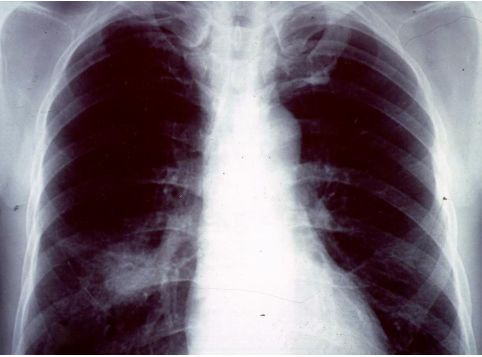

13. 39歲男性有多重性伴侶,因持續發燒及體重減輕3公斤,而且逐漸感到呼吸困難而入院,身體檢查發現口腔有白色珠菌 (Candida)感染,胸腔 X光如圖35 ,血液檢查結果: HIV Test :陽性、血液淋巴球比率: 8%、 CD3:34% 、CD4:0.2%、 CD8:36% 、CD19:4%,肺部灌洗液檢出囊胞蟲(Pneumocystis carinii),下列敘述何者為真?a. 囊胞蟲肺炎 ( Pneumocystis carinii pneumonia ) 典型表現為兩側肺門旁之浸潤,很快迅速進展成瀰漫性兩側肺部浸潤b. AIDS合併囊胞蟲肺炎患者的死亡率為單獨感染囊孢蟲肺炎者之三倍c. 所有囊胞蟲肺炎患者均需住院治療d. 大部HIV合併囊胞蟲肺炎病患的症狀均為突發性咳嗽,高燒而無呼吸困難症症狀e. Trimethoprium-Sulfamethoxazole仍為治療及預防囊蟲肺炎之首選藥物